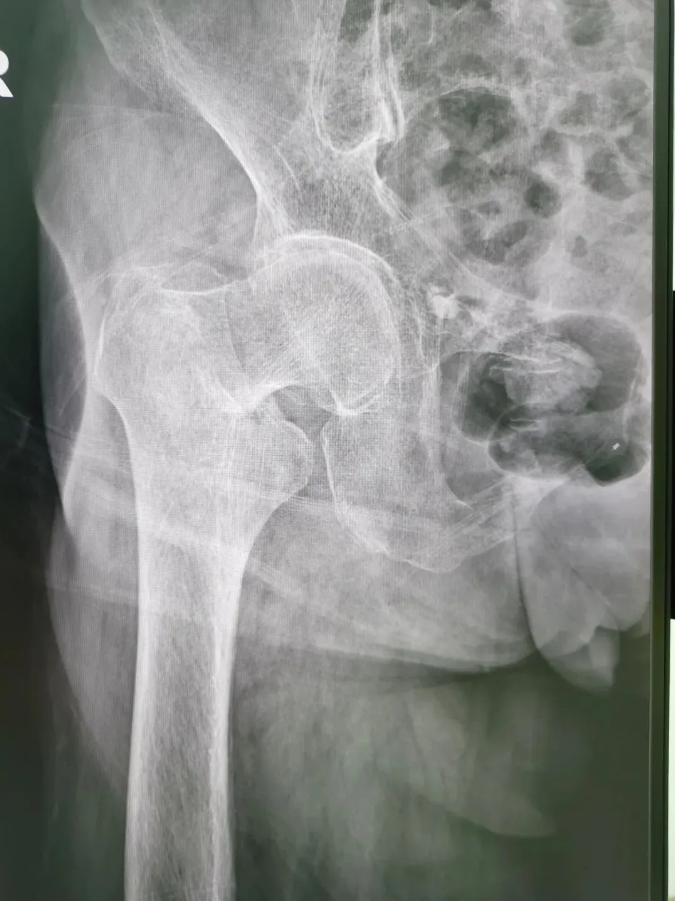

½ñÄê91ËêµÄ³ÂÆÅÆÅ£¬£¬£¬£¬£¬£¬£¬9Ô·ÝʱÔÚ¼ÒʧÉ÷ˤµ¹£¬£¬£¬£¬£¬£¬£¬ÓÒÍβ¿×ŵØ£¬£¬£¬£¬£¬£¬£¬µ±Ï¸ÐÓ¦÷Ų¿Ç¿ÁÒÌÛÍ´²¢Ô˶¯ÊÜÏÞ ¡£¡£¡£¡£¡£¡£ÎªÇó½øÒ»²½ÖÎÁÆ£¬£¬£¬£¬£¬£¬£¬µ½Ë³µÂÇå¾²Íâ¿ÆÒ½Ôº¹ÇÈýÇø¾ÍÕ£¬£¬£¬£¬£¬£¬¸ÃÇøÖ÷ÈÎÑîÉýƽÖ÷ÈÎΪÆäÕïÁÆ£¬£¬£¬£¬£¬£¬£¬±»Õï¶ÏΪ¡°ÓҹɹǾ±¹ÇÕÛ¡±£¬£¬£¬£¬£¬£¬£¬Ðè¾ÙÐÐÓҹɹǾ±¹ÇÕÛ¾­Æ¤±ÕºÏ¸´Î»¿ÕÐÄÂݶ¤ÄÚÀο¿ÊÖÊõ ¡£¡£¡£¡£¡£¡£

ÊõǰX¹â